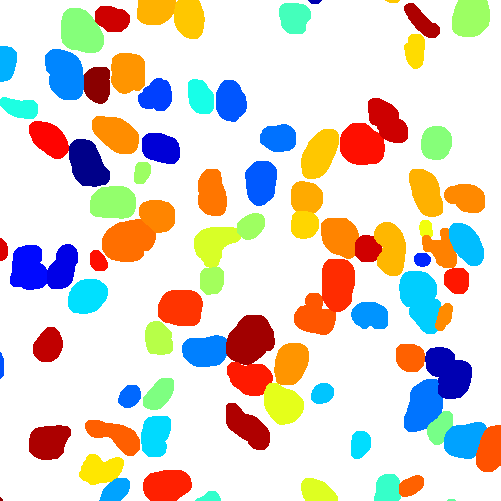

As an essential part of digital pathology, histopathology image analysis is playing increasingly important role in cancer diagnosis, which can provide direct and reliable evidence to diagnose the grade and type of cancer. This paper deals with nuclei segmentation, an important step in histopathological image analysis. The purpose of nuclei semgentation is not only counting the number of nuclei but also obtaining the detailed information of each nucleus. So unlike nuclei detection, here the outputs are the contour of each nucleus instead of only the position of their central points. Hence we can exactly extract each nucleus from the image and make it available for further analysis. For example, the features of the individual nucleus and the distribution of nuclei clusters can be used to grade and classify status of breast cancers [3, 4]. Because of appearance variation such as color, shape, and texture, nuclei segmentation from histopathological images could be very challenging, as illustrated in Fig.1, in which it is very challenging even for human to recognize and segment all nuclei within the images. Fig.1(a) and Fig.1(b) illustrate two histopathological images from different organs. Fig.1(c) and Fig.1(d) are two histopathological images from same organ but have different cancer grade.

Figure 6 shows how our method segments the nuclei step by step. The color variety is well controlled by the color normalization procedure. The prediction result shows clear nuclear areas and nucleus boundaries. In the final segmentation result and ground truth image, each nucleus is represented by a different color.